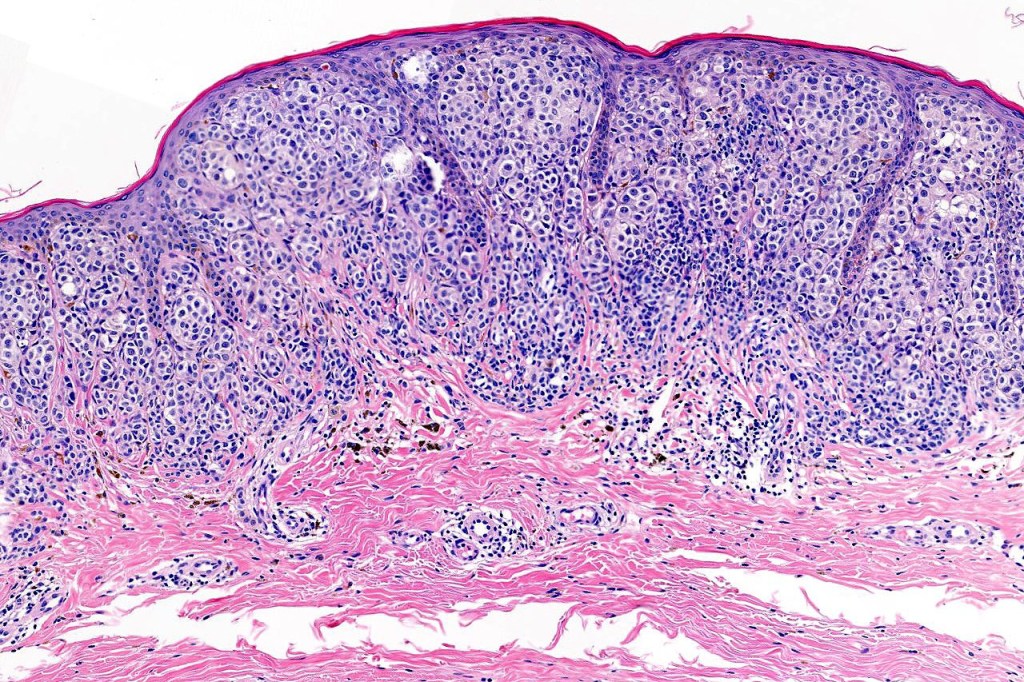

•Verrucous or dome-shaped, at low power, the lesion looks like a nevus

•Minimal or no junctional component

•Expansile nodules or diffuse

•Stretched & elongated rete ridges in verrucous variants

•Mimics type-A cells, (lesions which mimic type B nevus cells are often classified as small cell melanoma, this is important as the differential diagnosis is very different- see separate blog)

•Subtle or not so subtle impaired maturation with depth (sometimes this is evident at scanning magnification)